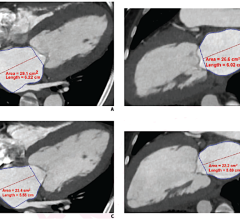

Vitrea software is Vital Images’ advanced visualization solution that creates 2D, 3D and 4D images of human anatomy from CT and MR image data. With this productivity-enhancing tool, physicians can easily navigate within these images to better understand disease conditions. The Vitrea software addresses specialists’ needs through various software options for cardiac, colon, vessel probe and other applications. In addition, Vitrea software utilizes an intuitive clinical workflow and automatic settings to improve speed and simplicity. Other capabilities and partnerships with PACS providers expanded physicians’ access to Vitrea software throughout an enterprise.